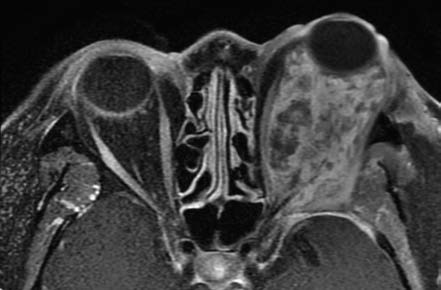

Figure 2 MRI imaging of left orbital arteriovenous malformation

Characteristic flow voids are observed within the lesion.

On CT imaging, orbital arteriovenous malformations often appear as poorly defined lesions with mixed-density signals, including hyperdense punctate or linear vascular structures. Some lesions may show hyperdense calcifications and hypodense areas of softening. Contrast-enhanced CT imaging often reveals worm-like enhanced clusters. MRI demonstrates the extent of the lesion and its anatomical relationships with great clarity. Both T1- and T2-weighted images exhibit characteristic flow voids, appearing as serpentine or globular low-signal areas within the lesion, surrounded by low signals from the feeding arteries and draining veins. Digital subtraction angiography (DSA) serves as the "gold standard" for diagnosing orbital arteriovenous malformations, providing detailed visualization of the feeding arteries, nidus, and draining veins.